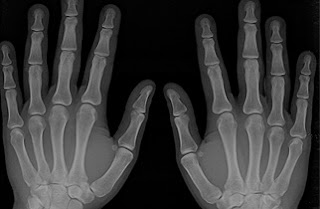

Os participantes passaram por testes de densidade óssea, em média um ano e meio após a primeira vez que apresentaram quaisquer sintomas sugestivos de EM. Os testes foram comparados com testes ósseos de cerca de 160 pessoas de idade, género e etnia semelhantes, mas que não têm a doença.

Dos indivíduos com EM, 51% foram diagnosticados com osteoporose ou osteopenia, em comparação com 37% do grupo controle. A osteoporose é uma doença em que a quantidade de massa óssea diminui substancialmente e desenvolve ossos ocos, finos e de extrema sensibilidade, mais sujeitos a fracturas. A osteopenia consiste na diminuição da densidade mineral dos ossos, precursora da osteoporose.